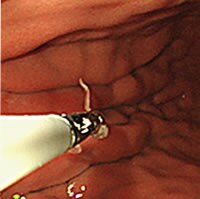

胃アニサキス症

前日から胃痛と嘔気があり、胃カメラをやったところアニサキス虫体がいました。その場ですぐに虫体を摘出し症状改善しました。

さばやイカなどを食べた後に胃が痛くなったら、アニサキスの可能性ありますのでご相談ください。